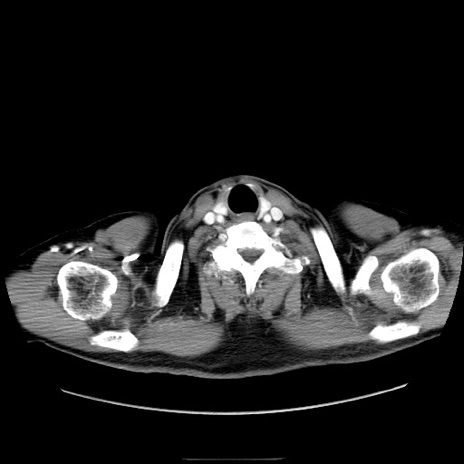

症例30(横断像)

【症例】80歳代男性

【主訴】臍周囲痛

【現病歴】約6時間前から臍下部痛が出現。次第に腹部膨隆・背部痛も生じてきたため来院。背部痛の場所は変化しない。

【身体所見】意識清明、BT 36.3℃、BP  131/87mmHg、P 87bpm、SpO2 100%(RA)、臍周囲自発痛・圧痛あり、反跳痛なし、自発痛部位に一致して板状硬あり、腹部膨隆、腸雑音減弱、CVA tenderness両側陰性。